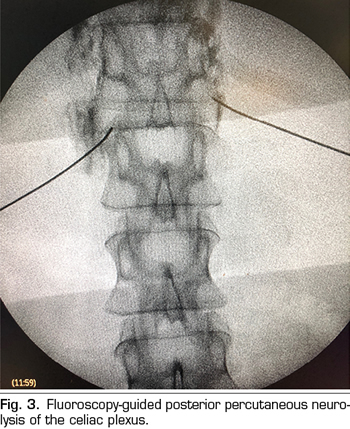

Figure 4